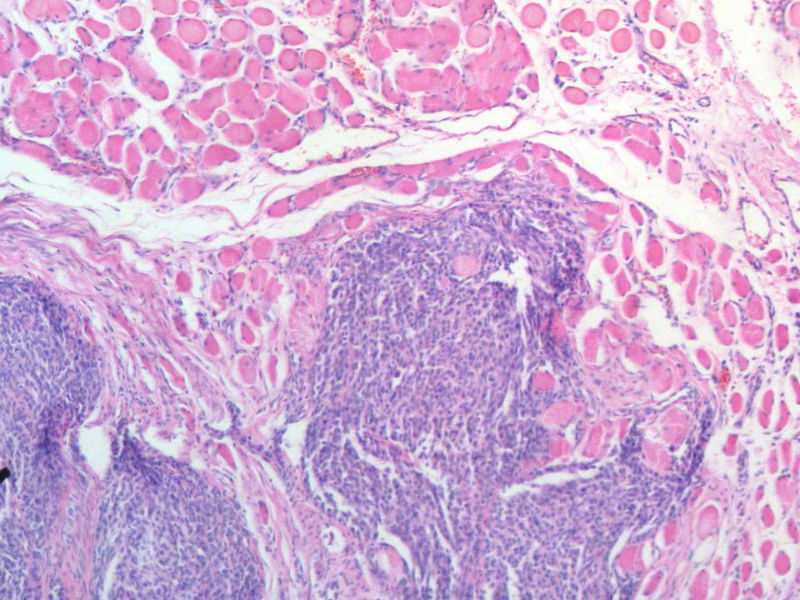

女,64岁,头晕半月,CT检查颅内左颞叶占位,侵犯颅骨和颞肌,手术切除肿物。肉眼,灰白色结节状肿物,3X3X2厘米,边界不清,切面灰黄色,质软。

特别提示:手术前曾做过介入肿瘤栓塞。镜下核分裂15/HP。脑左颞部占位图1

恶性脑膜瘤,有肌肉和骨的侵犯。

梭形细胞与上皮样漩涡状结构,富于细胞,见个别沙砾体,并见肿瘤性坏死。颅骨及其横纹肌等软组织内见肿瘤呈侵袭性生长。但细胞异型性不是很大。鉴别:

1)恶性脑膜瘤

2)非典型性脑膜瘤

由于非典型性脑膜瘤也可以发生地图状坏死,甚至侵袭性生长。需要计数核分裂数/10HPF,以资鉴别诊断。